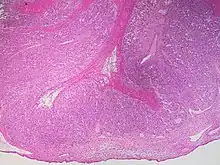

Histopathology of a corpus luteum cyst, H&E stain, low magnification, showing a convoluted layer of mainly granulosa lutein cells, surrounding a fibrous to hemorrhagic center.